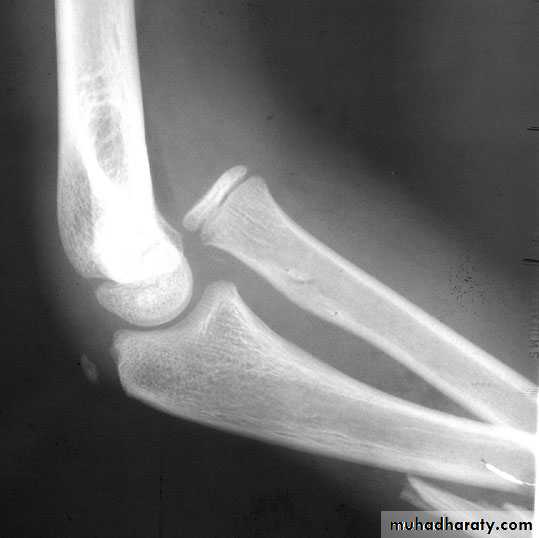

Galeazzi fracture dislocation of the radius

It is caused by fall on the hand , there is fracture in the lower third of the radius and dislocation of the inferior radio- ulnar joint .Clinically : it is much more common than monteggia , prominence and tenderness over the lower end of the ulna is an important point in examination .

Treatment : the most important point is to restore the length of the fractured radius , other wise the dislocation will not reduced .

In children close reduction is possible but if fail , then open reduction and fixation .

In adult , the treatment will be by open reduction and internal fixation .